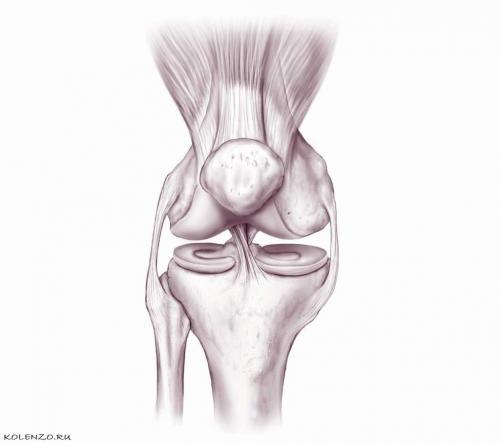

Коленный сустав сформирован мыщелками бедра с эксцентричной кривизной, а также суставными поверхностями надколенника и большеберцовой кости. Суставные поверхности мыщелков, относящихся к большеберцовой кости, между собой разделены межмыщелковым возвышением с задними и передними бугорками, в которых прикрепляются мениски и крестообразные связки .

Внутрисуставные образования сустава колена - это жировое тело, мениски и крестообразные связки. Жировое тело располагается между фиброзной капсулой, синовиальной оболочкой и связкой надколенника. Жировые тела выполняют роль амортизаторов, которые в процессе движений в суставе переносят напряжение синовиальной оболочки. Они также богаты нервами, кровеносными и лимфатическими сосудами.

Мениски , образованные волокнистым хрящом, повышают степень вогнутости большеберцовой кости. Медиальный мениск имеет полулунную форму, а латеральный – кольцевидную. Латеральный мениск несколько шире, чем мениск медиальный. Его передний рог прикреплен к наружной части медиального межмыщелкового возвышения и передней крестообразной связки (ПКС), а задний рог крепится непосредственно к латеральному межмыщелковому возвышению. Важно знать, что медиальный мениск – полукруг, больший по размеру, чем мениск латеральный. Узкий передний рог данного мениска прикрепляется к медиальному возвышению, находящемуся перед ПКС, а более широкий задний рог крепится к латеральному возвышению впереди задней крестообразной связки (ЗКС), а также кзади от заднего рога латерального мениска. Тем временим, передние рога менисков отделяет ПКС, задние – прикреплены в положении рядом. Наружный край медиального мениска очень прочно сращен с суставной капсулой. Малая подвижность мениска, связанная с этим, предопределяет частое возникновение его разрывов. Латеральный мениск на протяжении 1-1,5 см в наружном отделе отделяется посредством сухожилия подколенной мышцы от капсулы сустава, что обеспечивает большую его подвижность, за счет чего и предохраняет мениск от травм.

Коленный сустав (art. genus) наиболее крупный и сложный по строению. Он образован бедренной, большеберцовой костями и надколенником. Суставные поверхности медиального и латерального мыщелков бедренной кости сочленяются с верхней суставной поверхностью большеберцовой кости и надколенником. Внутри сустава имеются полулунной формы внутрисуставные хрящи — латеральный и медиальный мениски, которые увеличивают конгруэнтность сочленяющихся поверхностей, а также выполняют амортизирующую роль.

Латеральный мениск (meniscus lateralis) более широкий, чем медиальный мениск (meniscus medialis). Латеральный край менисков сращен с капсулой сустава. Внутренний истонченный край менисков свободный. Передний и задний концы менисков прикреплены к межмыщелковому возвышению большеберцовой кости. Передние концы менисков соединяются поперечной связкой колена

(lig. transversum genus).